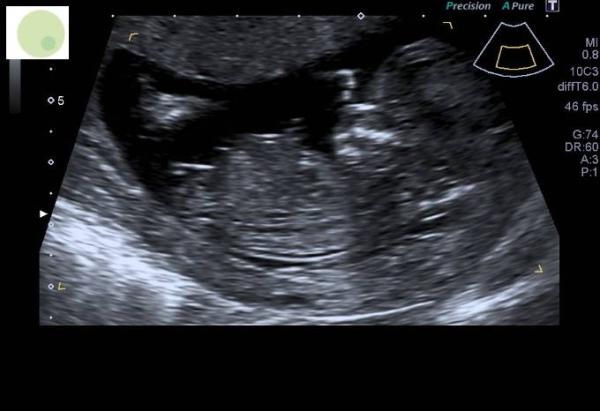

ja ich zeig dir mal mein Bild von der Nackenfaltenmessung- mir wurde gesagt es wird ein Junge weil das da vorne so aufsteht & bei Mädchen sind so Waagrechte striche wie auf deinem Bild ich glaub das ist die sogenannte NUB Theorie! Aber die werden sich schon auskennen

Bild zu

Ach interessant. Ich hab die Nub Theorie nie so richtig verstanden aber so wie bei deinem Baby sah das bei uns definitiv nicht aus. Ich denke auch, dass die sich da auskennen. In zwei Wochen weiß ich es dann auch definitiv, weil wir das Geschlecht noch beim NIPT mitbestimmen lassen P.S.: dein US Foto sieht ja total süß aus LG